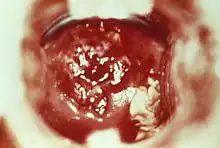

HSV cervicitis

To diagnose cervicitis, a clinician will perform a pelvic exam. This exam includes a speculum exam with visual inspection of the cervix for abnormal discharge, which is usually purulent or bleeding from the cervix with little provocation.[4] Swabs can be used to collect a sample of this discharge for inspection under a microscope and/or lab testing for gonorrhea, chlamydia, and Trichomonas vaginalis. A bimanual exam in which the clinician palpates the cervix to see if there is any associated pain should be done to assess for pelvic inflammatory disease.[3]